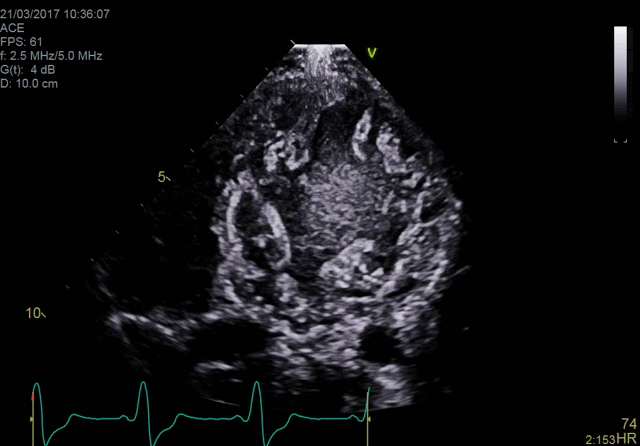

Ultra-high single-beat volume rates With TEE procedures growing, so is the need to find ways to achieve the benefits of 4D imaging without compromising productivity. VmaxTM enabled by cSound™ 2.0 offers ultra-high 4D volume rates acquired in single beat acquisition with no loss of image quality. Elimination of ECG gated multibeat/stitching acquisition provides enhanced overview of structures and function in cases with high and/or irregular heart rhythm - which potentially reduces interventional procedure time and improves patient outcomes.

4D TEE color imaging with Vmax